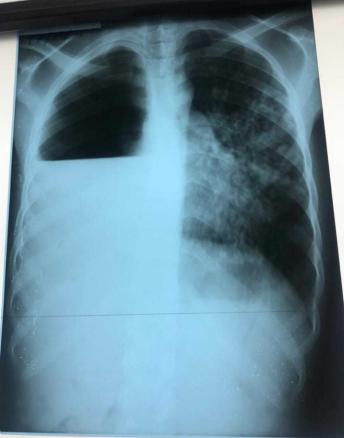

C'est une complication rare mais grave de la tuberculose pulmonaire évolutive. Le diagnostic est facilement évoqué quand s’associent au pneumothorax des lésions fibro-cavitaires parenchymateuses.